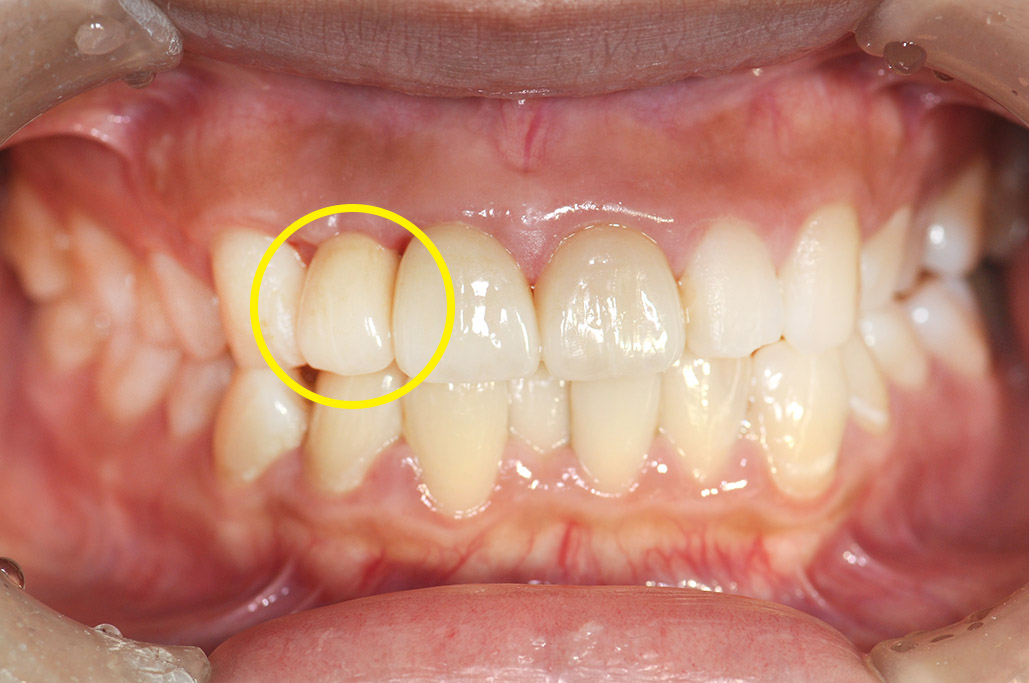

交通事故による前歯の欠損を復元した患者さまの症例です。